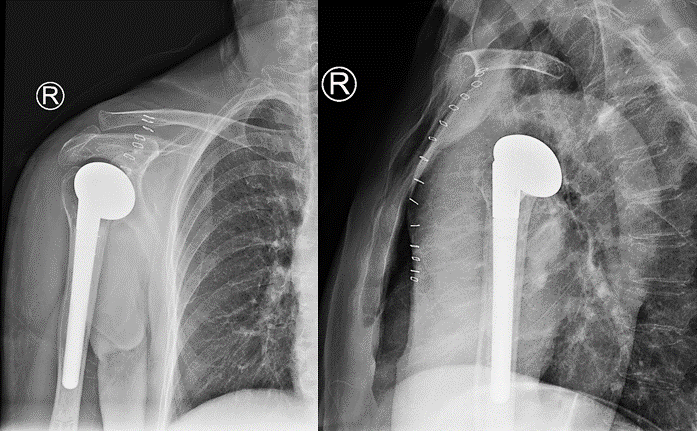

术后X线片显示人工肱骨头假体位置满意